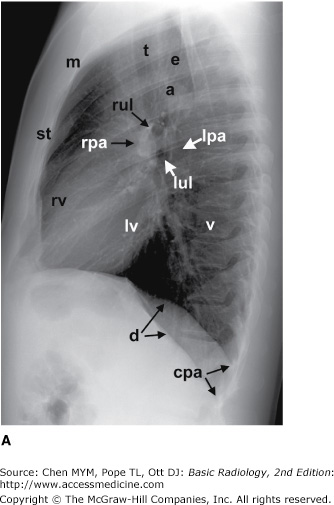

The two sides connect at the sternum, or b. Radiology Chest Xray Normal

The epidermis is the outermost layer that provides a protective, waterproof seal over the body. Chapter 4 Radiology Of The Chest Radiology Key

Chapter 4 Radiology Of The Chest Radiology Key from radiologykey.com